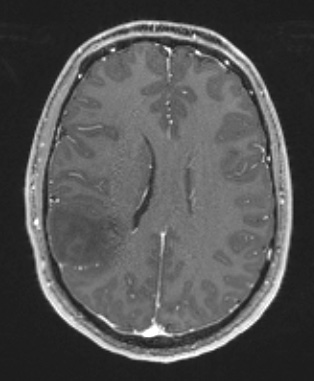

17A2 (Case 17) T1W - Copy

The T1-weighted contrast applied scan fails to show enhancement.